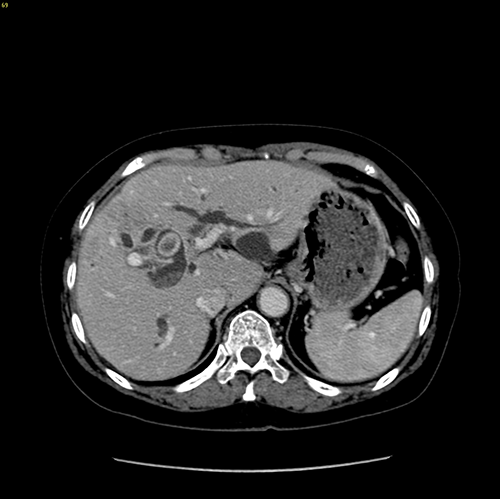

右肝胆管结石,胆总管结石---右半肝切除、T管引流